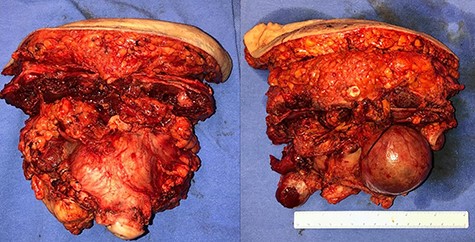

In April 2020, the surgery was performed, with pan-hysterectomy, excision of the AW and skin, pelvic peritonectomy, cecectomy (due to local involvement), partial cystectomy, Hartmann rectosigmoidectomy (Figs 4 and 5), followed by AW partial closure and an intraperitoneal onlay mesh (Open IPOM) in a bridged position with Bard Mesh/BD Sepramesh. Abdominoplasty was performed to allow skin coverage (Figs 6–10). The patient stayed in hospital for 18 days and presented urinary retention. Definitive anatomopathological was HGSC, infiltrating uterus, AW, cecum, rectosigmoid and obturator lymph node metastasis. After cytoreduction, she underwent chemotherapy (carboplatin plus docetaxel).

Surgical specimen of pan-hysterectomy with excision of the abdominal wall and cecectomy.